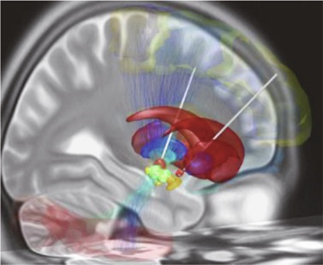

图源:维基共享;DBS电极(白色)被手术植入到大脑两个半球的丘脑下核(橙色)。这些大脑区域在促进和抑制某个运动意图方面发挥主要作用